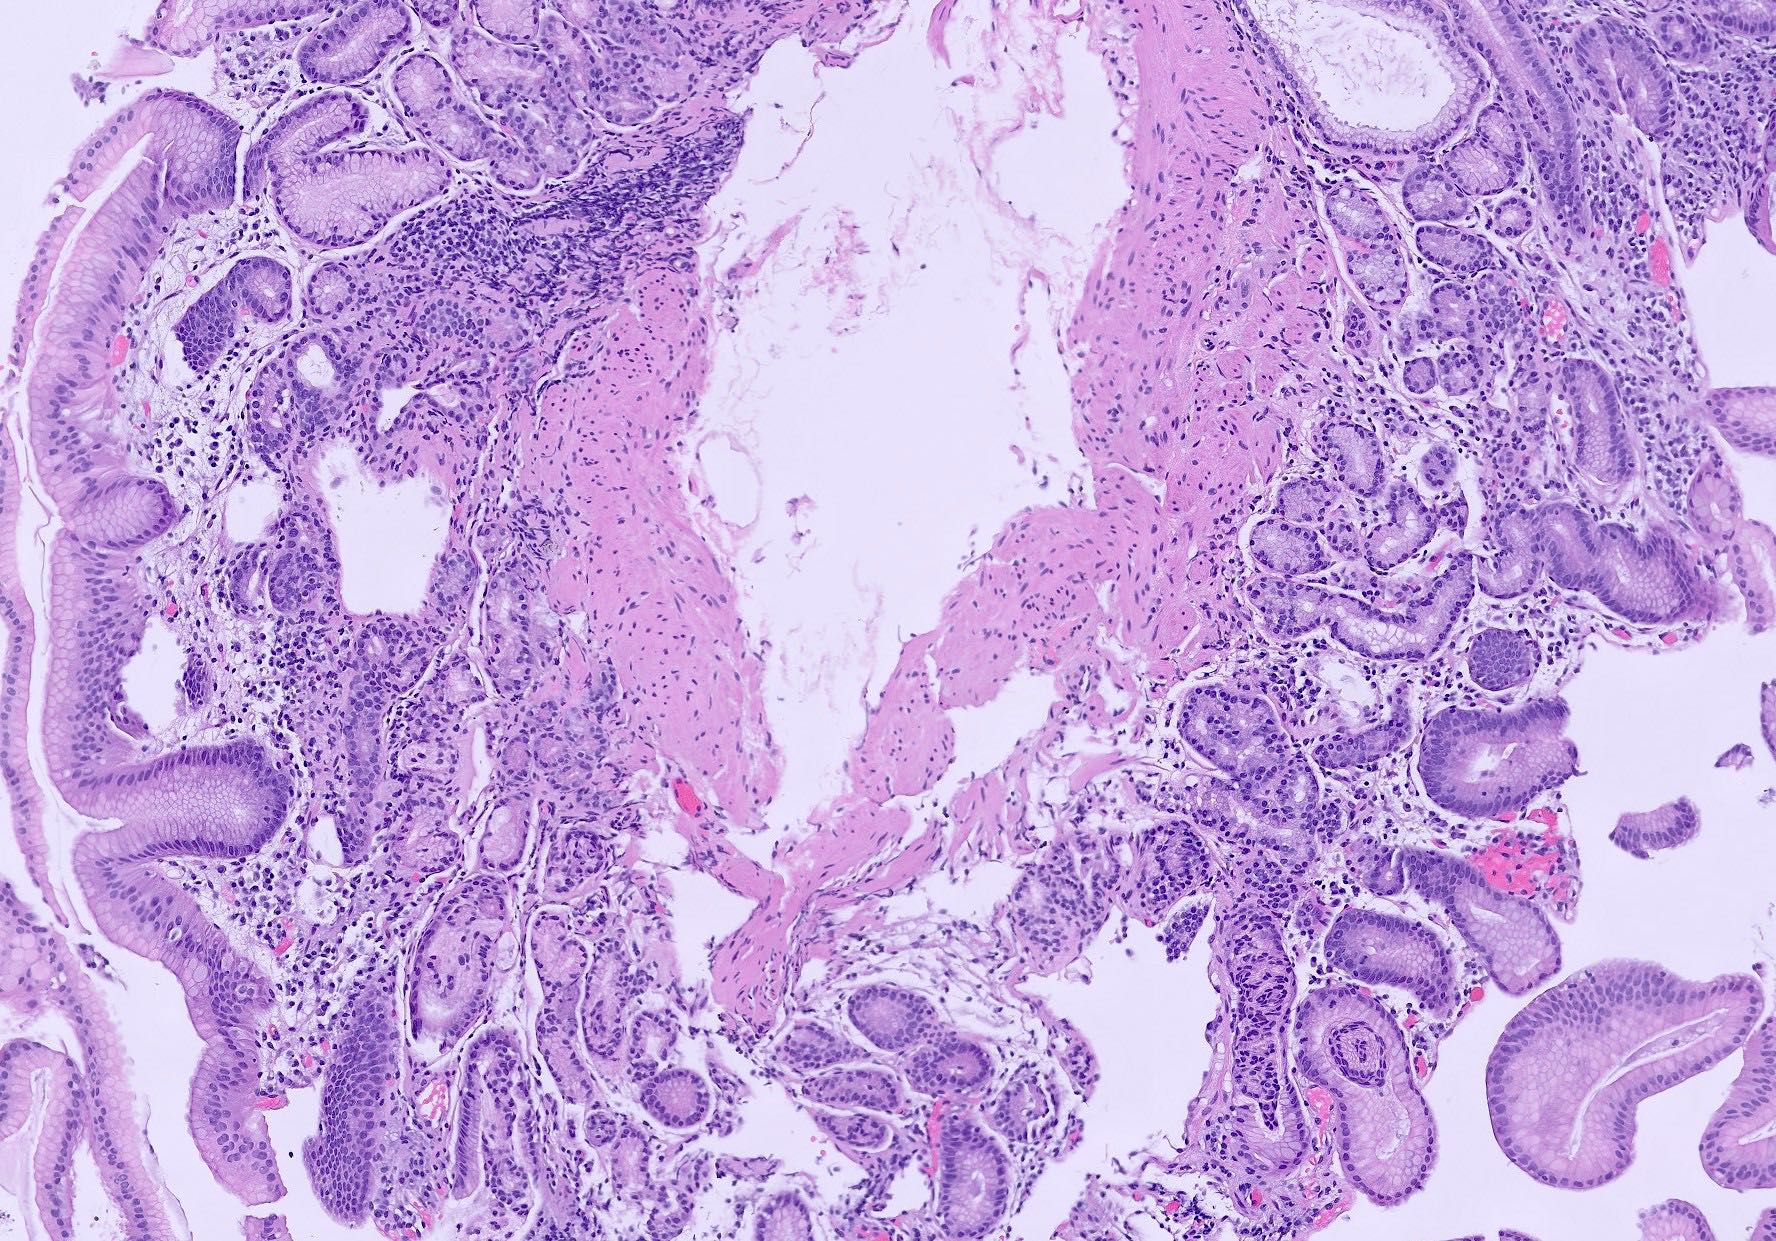

Points of Recognition

- 1Lymphoplasmacytic infiltrate in lamina propria

- 2Neutrophil infiltration (activity) in pit epithelium (H. pylori)

- 3Glandular atrophy and intestinal metaplasia in chronic cases

- 4H. pylori organisms on special stains (Giemsa)

- 5Lymphoid follicles (especially in H. pylori)

Image reference: PathologyOutlines.com

- Chronic gastritis: lymphoplasmacytic infiltrate, lymphoid follicles, glandular atrophy

- H. pylori gastritis: organisms visible on Giemsa stain, activity (neutrophils) in pit epithelium